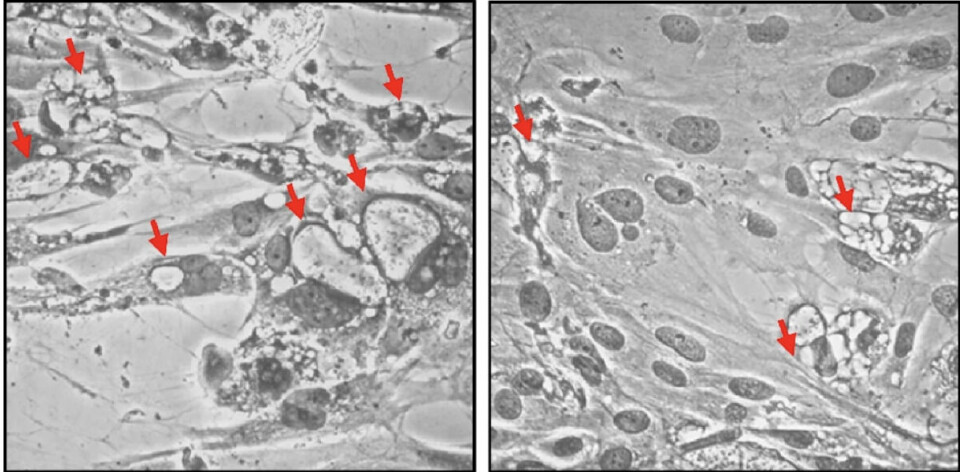

Posteriormente, para investigar más a fondo el papel de la transferrina, los expertos generaron células fagocíticas knock-out para el gen de la transferrina (TF-KO) mediante CRISPR/Cas9. Los ensayos de infección in vitro revelaron que, en comparación con las células sin intervención (TF-WildType), las células TF-KO presentaron efectos citopáticos reducidos, menor formación de vacuolas que contienen P. salmonis y una viabilidad mejorada.

“Sorprendentemente, no se detectaron diferencias en la carga bacteriana ni en la expresión génica relacionada con el hierro entre las células TF-KO y TF-WT, lo que indica que la alteración de la transferrina no alteró directamente la homeostasis del hierro”, señalaron al respecto los investigadores.